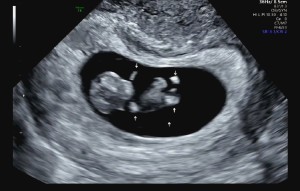

초음파사진

닉네임_류*영_3

2025-03-19

8

1